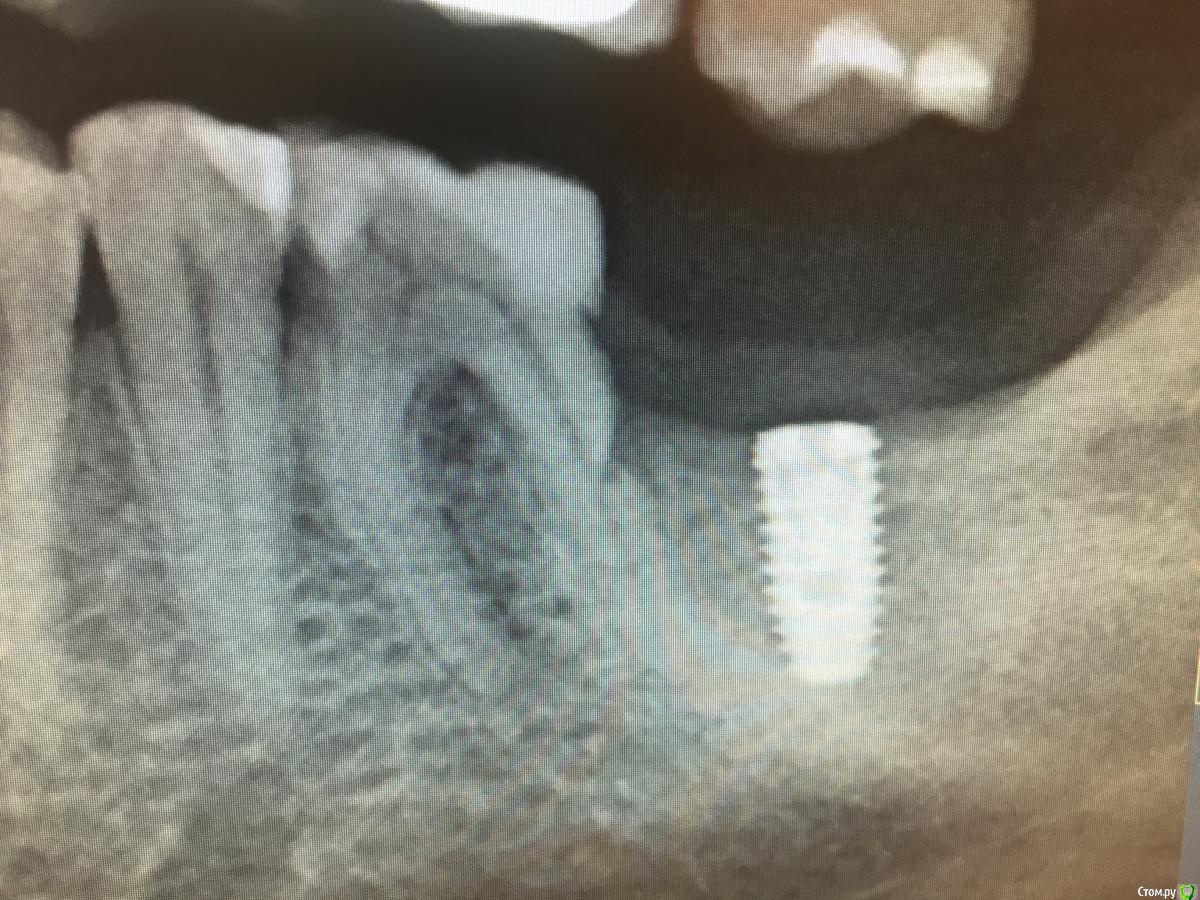

АнтонТЛТ Опубликовано 31 мая, 2020 Поделиться Опубликовано 31 мая, 2020 Был не давно фейл. Шестерка с пропилом дистального корня. Решили рискнуть и поставили 7ку. Всё было ок. Но потом кость ушла до уровня пропила и имплантат начал оголяться. В итоге шестерка и имплантат удалены. Буду ставить 2 имплантата. Если будет в той клинике смена на следующей неделе, то скину снимки. 2 Ссылка на комментарий

АнтонТЛТ Опубликовано 16 июня, 2020 Поделиться Опубликовано 16 июня, 2020 Был не давно фейл. Шестерка с пропилом дистального корня. Решили рискнуть и поставили 7ку. Всё было ок. Но потом кость ушла до уровня пропила и имплантат начал оголяться. В итоге шестерка и имплантат удалены. Буду ставить 2 имплантата. Если будет в той клинике смена на следующей неделе, то скину снимки.Постоянно забывал сфоткать 1 Ссылка на комментарий